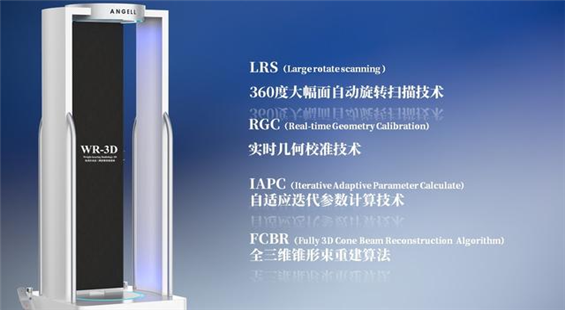

388vip太阳集团科技基于数字化X线摄影技术创新的WR-3D负重位多角度三维扫描系统

388vip太阳集团科技WR-3D负重位动态三维摄影技术